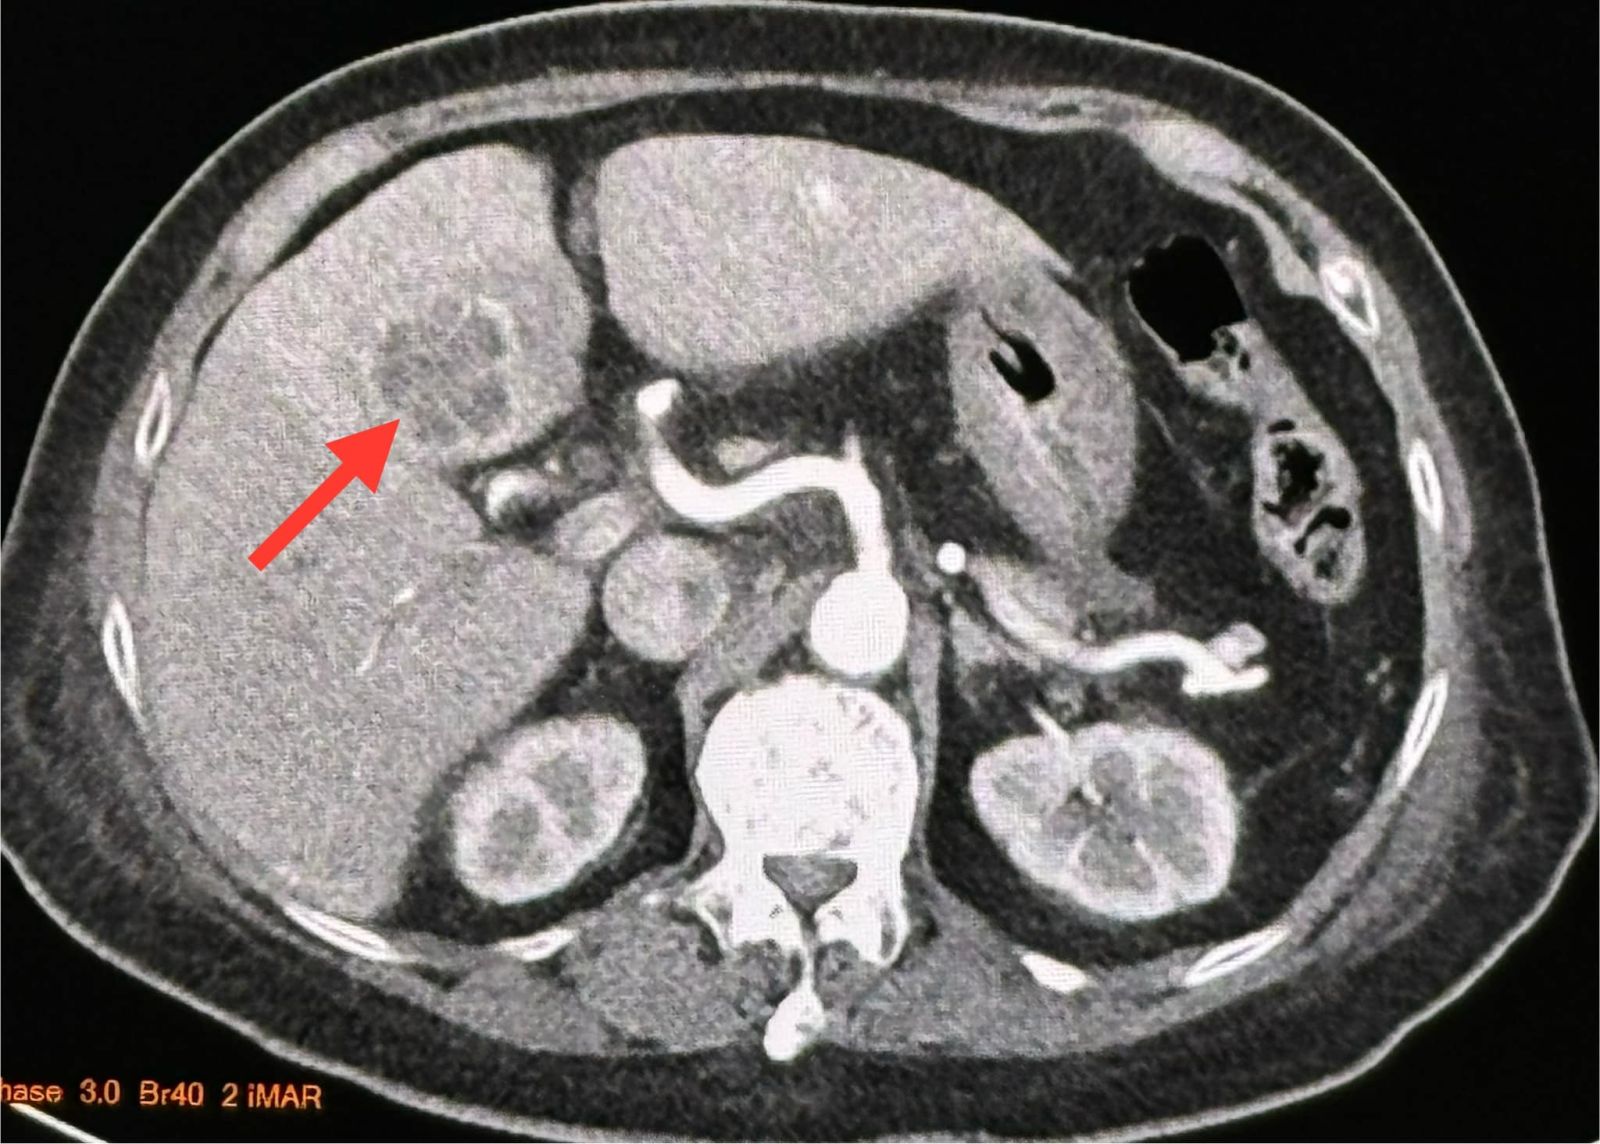

หมอมนูญ เปิดเผยด้วยว่า ผลตรวจร่างกาย มีไข้สูง ฟังปอดปกติ คลำท้องไม่เจ็บ ตับไม่โต เจาะเลือด เม็ดเลือดขาวในเลือดสูง 29,300 ค่าเอนไซม์ตับสูงเล็กน้อย SGOT 87, SGPT 73 ทำอัลตราซาวด์ช่องท้องด้านบน พบก้อนในตับข้างซ้ายขนาด 2.8 × 2.4 × 2.4 เซนติเมตร ส่งเลือดเพาะเชื้อ ขึ้นเชื้อแบคทีเรีย Klebsiella pneumoniae เอกซเรย์คอมพิวเตอร์ช่องท้อง 2 วันต่อมา พบก้อนขนาด 3.3 × 3.3 × 2.8 ซม.ในตับข้างซ้าย เข้าได้กับฝีในตับ

แพทย์วินิจฉัยว่า ป่วยเป็นฝีในตับ จากเชื้อแบคทีเรีย Klebsiella pneumoniae และติดเชื้อในกระแสเลือด ทำให้ช็อก ความดันต่ำ การรักษาให้น้ำเกลือ ยากระตุ้นความดันโลหิต และ ยาปฏิชีวนะ ceftriaxone (ทดสอบแล้วในห้องปฏิบัติการว่าเชื้อตัวนี้ไวต่อยา) ทางหลอดเลือดดำ ได้ทำการเจาะหนองจากฝีในตับผ่านทางหน้าท้อง ได้หนอง 2 ซีซี ส่งหนองเพาะเชื้อขึ้นเชื้อ Klebsiella pneumoniae ตัวเดียวกับในเลือด